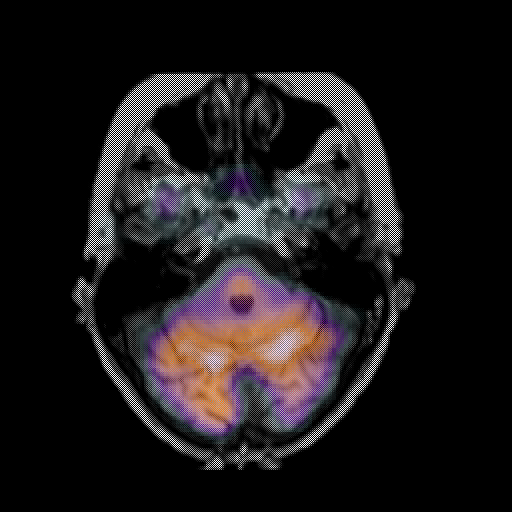

overlay: Slice 14

Slice 14

MRCBFCBF with

T1PDT2T1PDT2